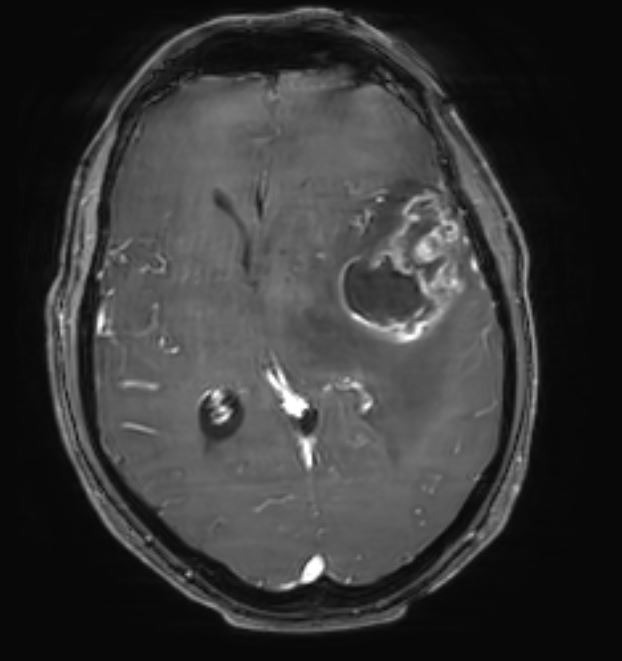

Ασθενής 52 ετών με εξεργασία εγκεφάλου ύποπτη για γλοιοβλάστωμα και διαταραχές ομιλίας μικτού τύπου.

Αποφασίστηκε η διενέργεια κρανιοτομίας για αφαίρεση του όγκου. Λόγω της εγγύτητας της βλάβης με κρίσιμες (eloquent) περιοχές του εγκεφάλου όπως είναι τα κέντρα και δεμάτια του λόγου, η νήσος του Reil και η πυραμιδική οδός (οδός της κίνησης άνω και κάτω άκρων) το χειρουργείο έγινε με τον ασθενή ξύπνιο (awake craniotomy) και με τη χρήση διεγχειρητικού υπερήχου, ανοσοφθορισμού 5-ALA και διεγχειρητικού νευροφυσιολογικού ελέγχου (neuromonitoring).

Η μετεγχειρητική μαγνητική τομογραφία ανέδειξε πλήρη εξαίρεση του όγκου.